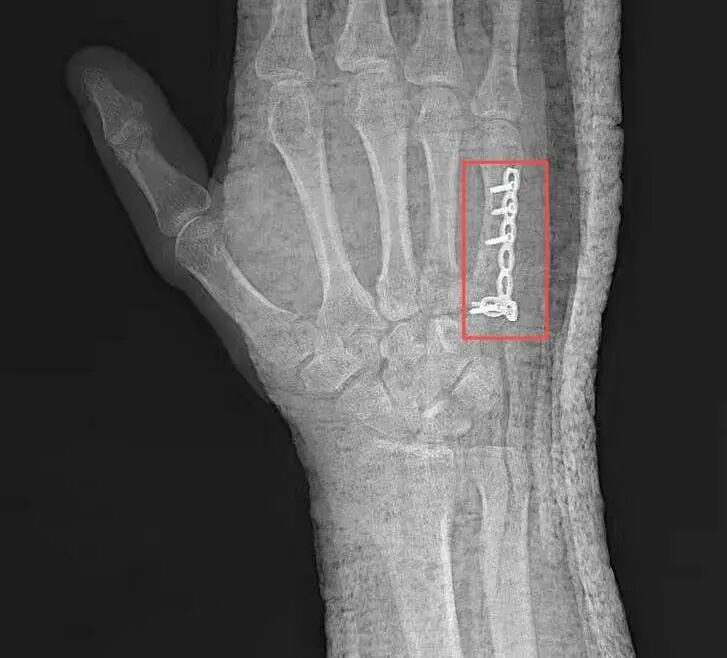

2025年3月8日,夏先生因意外受伤前往玉溪市中山医院骨科就诊,经详细检查会诊,诊断夏先生为右手第五掌骨骨折。骨科团队迅速为其制定个性化治疗方案,并于3月13日成功实施“掌骨骨折切开复位钢板内固定术”,手术由曾润华与韩振宏两位医生主刀。凭借丰富的临床经验与精湛的微创技术,两位医生顺利完成手术。术后,夏先生恢复良好,疼痛明显减轻。同时,医护人员每日密切监测夏先生病情、耐心指导其进行康复训练,夏先生手部功能逐步恢复,于3月17日顺利出院。

术后患者右手第五掌骨处固定复位钢板